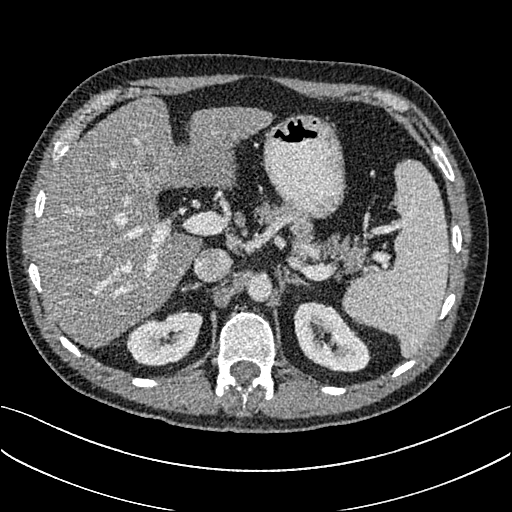

To demonstrate the effectiveness of the proposed network, we perform the qualitative comparisons over three representative abdominal images presented in Figs. 3, 5 and 7. For better evaluations of the image quality with different denoising models, zoomed regions-of-interest (ROIs) are marked by red rectangles and shown in Figs. 4, 6 and 8 respectively. Note that all results from different denoising models focus on two aspects: content restoration and noise-reduction. All CT images in axial view are displayed in the angiography window [-160, 240]HU.

The real NDCT images and corresponding LDCT images are presented in Figs. 3a and 3b. As observed, there are distinctions between ground truth (NDCT) images and LDCT images. Figs. 3a and 7a show the lesions/metastasis. Fig. 5a presents focal fatty sparing/focal fat. In Figs. 4a, 6a and 8a, these lesions can be clearly observed in NDCT images; in contrast, from Figs. 4b, 6b, and 8b, it can be seen that the original LDCT image is noisy, and lacks structural features for task-based clinical diagnosis. All adopted denoising models suppress noise to some extent.

Mean-based methods can effectively reduce noise, but the side effect is impaired image contents. In Fig. 3c, -net greatly suppresses the noise, but blurs some crucial structural information in the porta hepatis region. Meanwhile, some waxy artifacts can still be observed in Fig. 6c. -net does not produce good visual quality because it assumes that the noise is independent of local characteristics of the images. Even though it retains high SNR, its results are not clinically preferable. Compared with -net, in Figs. 3d and 5d, it can been seen that -net encourages less blurring and preserves more structural information. However, as observed in Fig. 4d, it still over-smooths some anatomical details. Meanwhile, in Fig. 6d, there are some blocky effects marked by the blue arrow. The results obtained by RED-CNN [35] deliver high SNR but blur the vessel details as shown in Figs. 4i and 6i.

For SL-based methods, as observed in Figs. 3e and 5e, SL-net generates images with higher contrast resolution and preserves texture of real NDCT images better than -net and -net. However, Figs. 4e and 6e show that SL-net does not preserve the structural features well, and there still remain small streak artifacts. Subsequently, in Figs. 4e and 4f, SL-net and MSL-net have low frequency image intensity variance because SSIM/MS-SSIM is insensitive to uniform biases [49, 51]. On the other hand, -net preserves the overall image intensity, but it does not preserve high contrast resolution well as SL-net and MSL-net do.

From Figs. 7 and 8, we can see mean-based and SL-based methods work well with effective noise suppression and artifact removal. However, the illustrations in Fig. 8 show that these methods blur the local strutural features. Our proposed SMGAN-based methods present a better edge preservation than the competing methods.